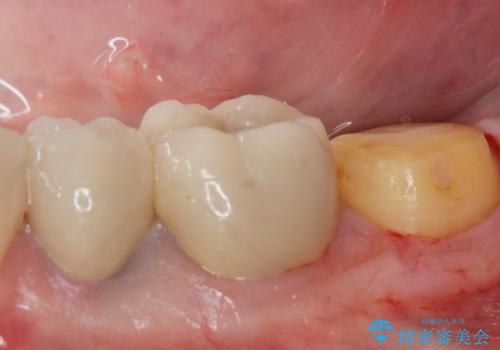

- 過去に治療したゴールドの詰め物が取れて来院。取れたのは2回目だそうです。レントゲンでは適合が良いので再装着可能だったが、

もう取れたくないとの事だったので被せ物のご案内をしました。ゴールドの被せ物の希望だったのでゴールドクラウンでの治療になりました。

適合の良いゴールドクラウンが入りました。

ゴールドは適合が良く、割れる心配もありません。

また、虫歯になるリスクも銀歯と比べて低くなります。